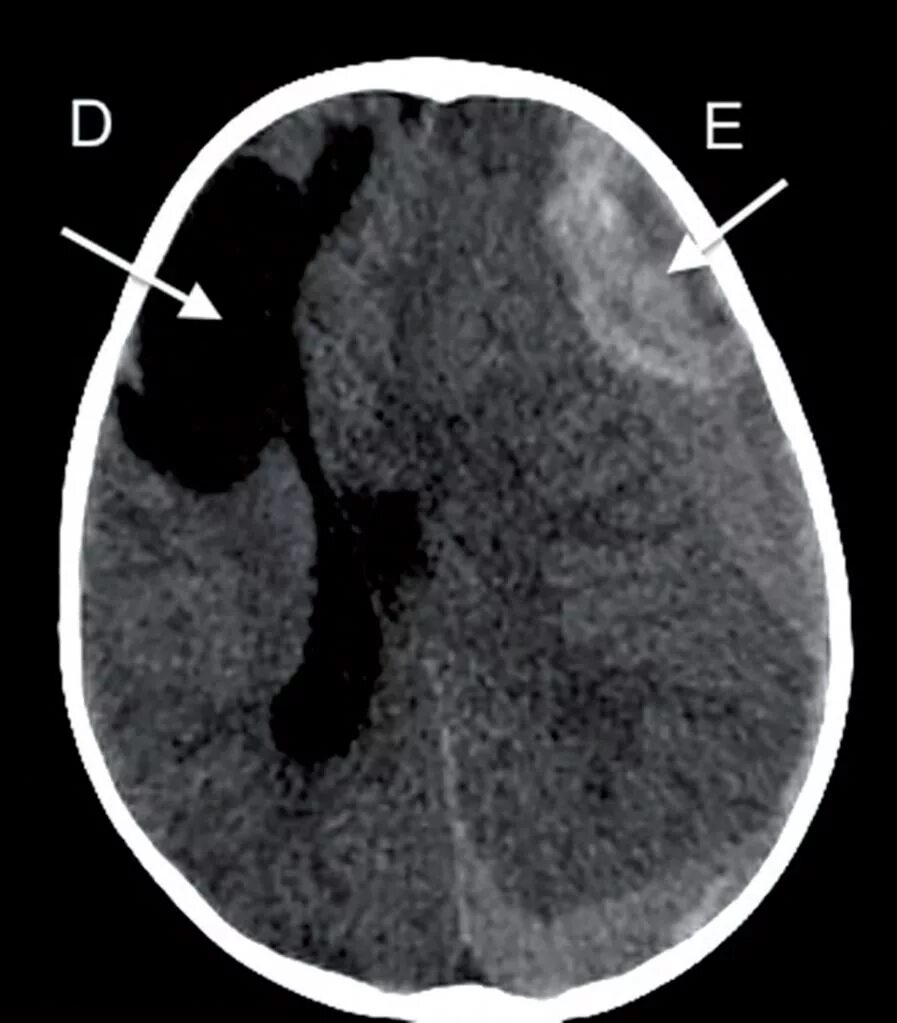

Ишемическом инсульте кровоизлияние